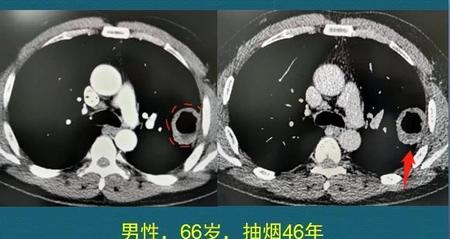

这是一位肺鳞癌,咳嗽吐血,已经手术治愈3年半了。